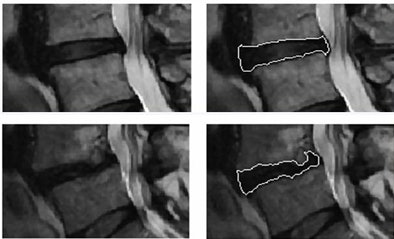

| Lumbar disk segmentation in the study was based on a hybrid algorithm combining fuzzy clustering techniques with a probabilistic disk atlas. Shape and textural features were extracted from each segmented disk region to quantify its properties. |

The disks depicted on MRI were extracted from the rest of the dataset using an Atlas process. Then shape and textural features were extracted from each segmented disk region including region descriptors, Hu's moments, Fourier descriptors, first-order textural features, and co-occurrence features.